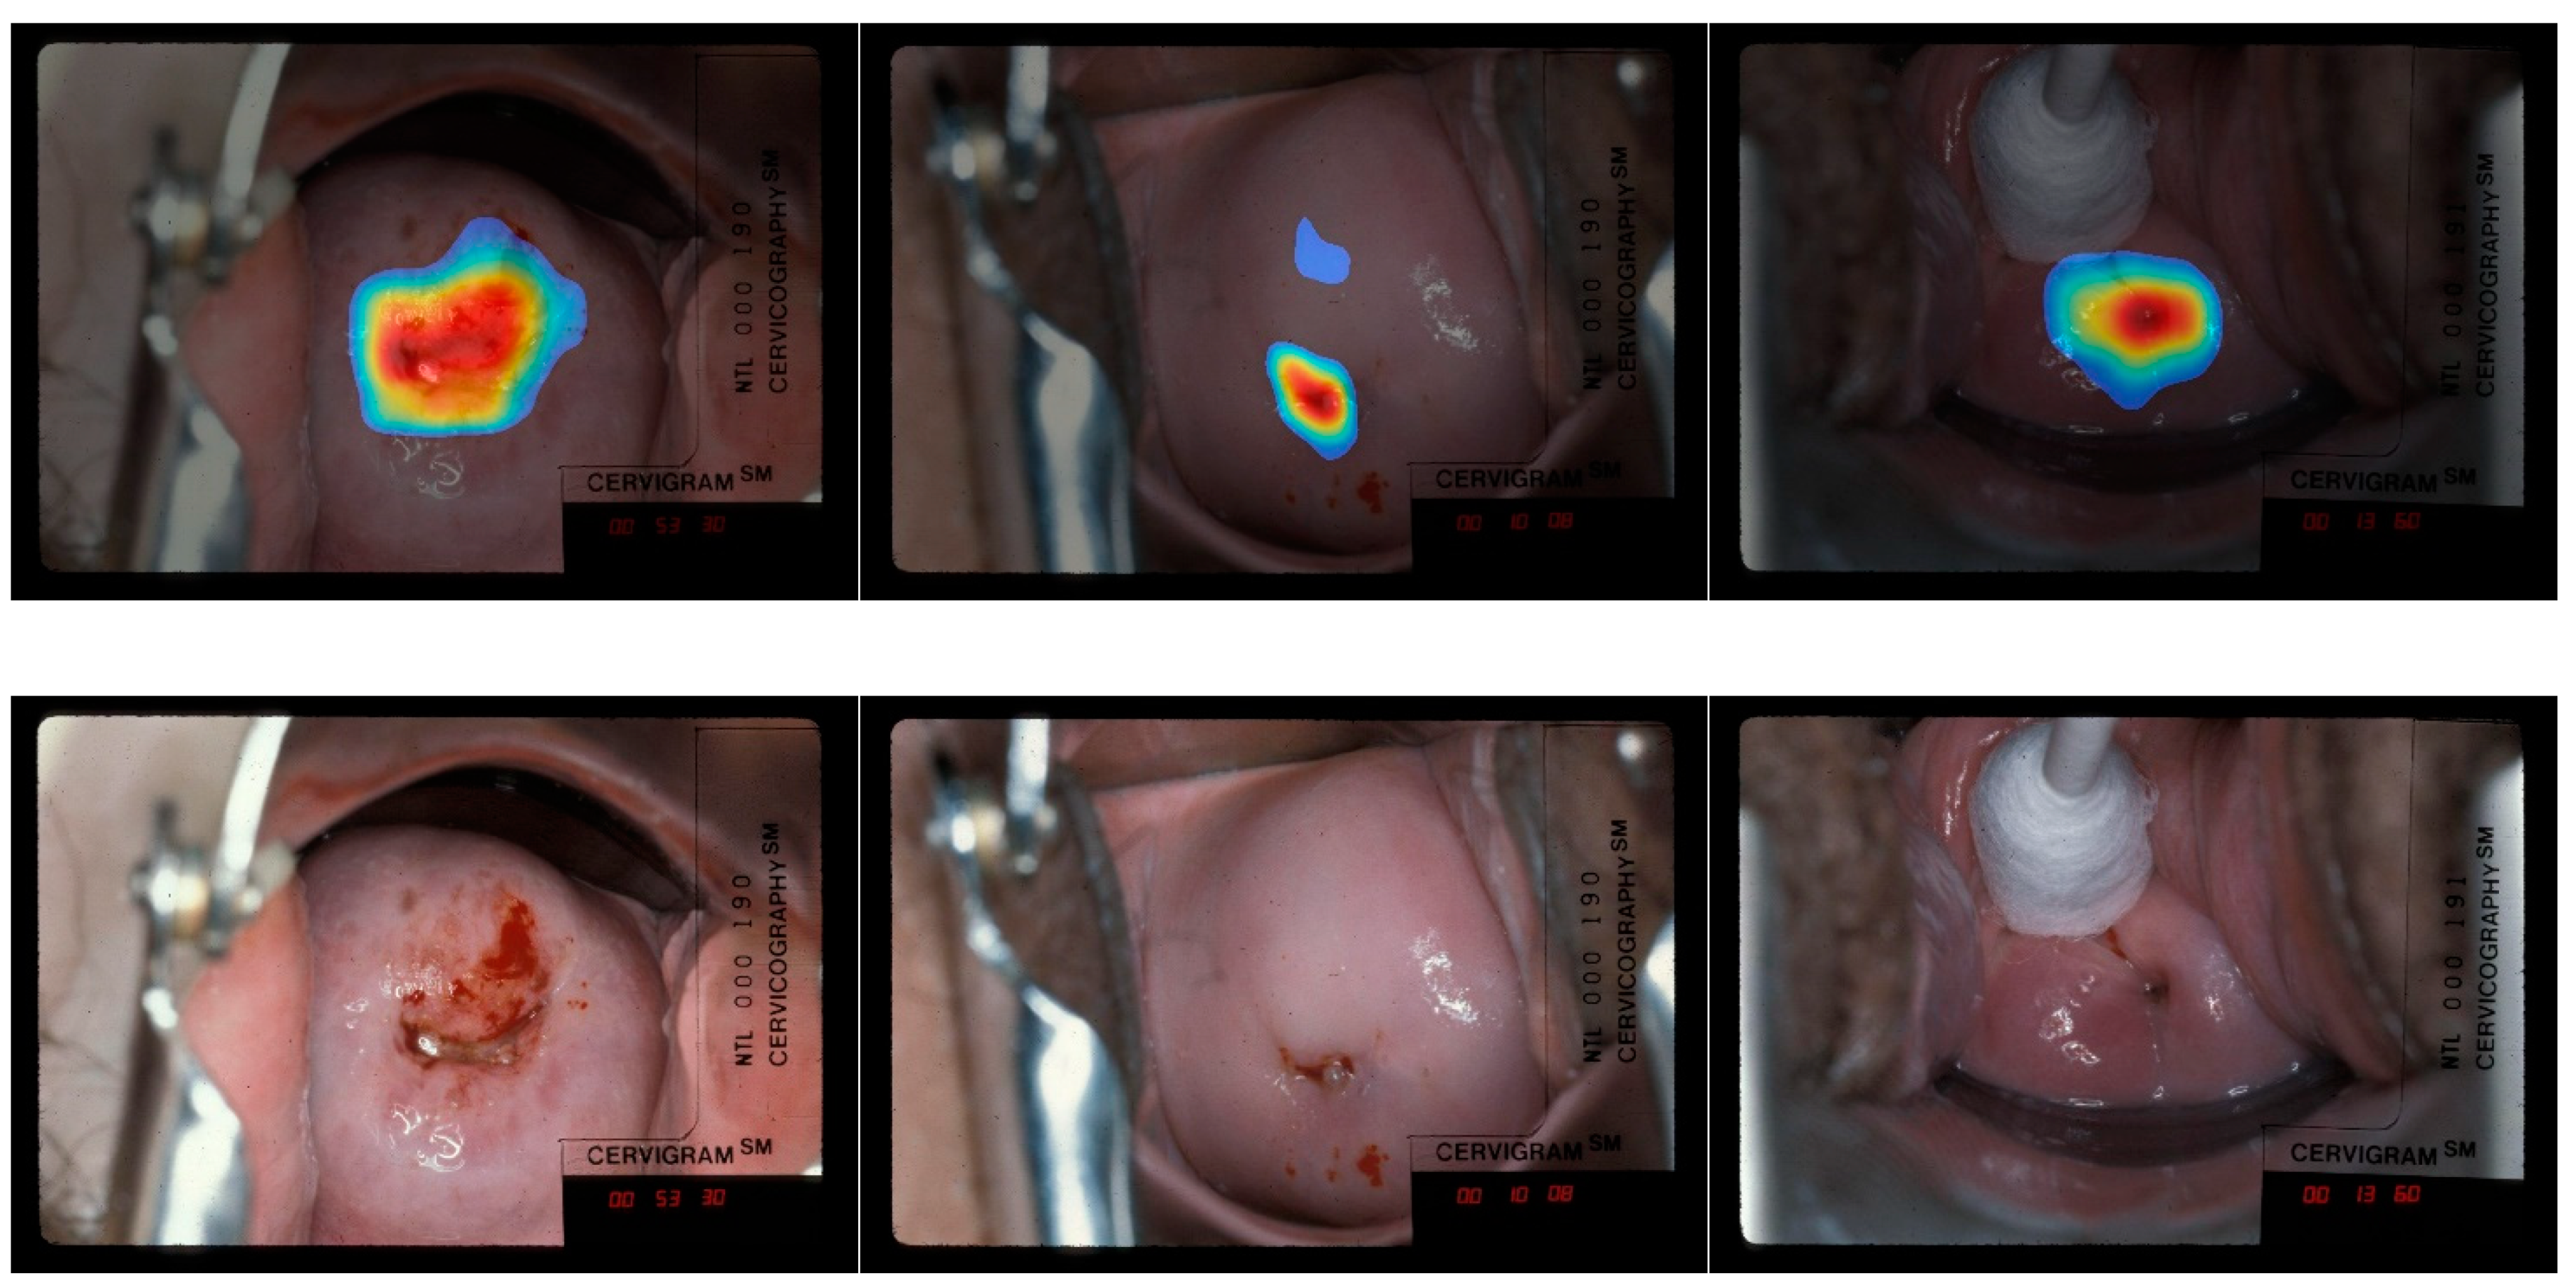

- The heatmaps from both CRM and CAM shows that the most relevant image pixels for making correct classification are those in or around the os and T-Zone.

- Compared to CAM, the CRM (1) visualizes and focuses more on the area around the os and T-zone; and (2) generates fewer heatmaps that the human expert disagrees with.

4.3.1. CAM vs. CRM Heatmaps

4.3.2. Out of Region of Interest (RoI) and Insufficient Coverage